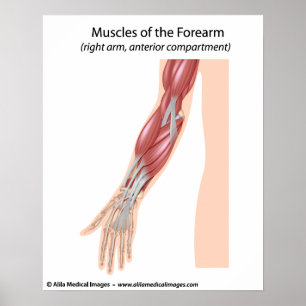

Muskeln des Unterarms, beschriftet Diagramm Poster

PreisCHF 71.25

Vorarmmuskulatur-Vorderansicht Poster

PreisCHF 67.90